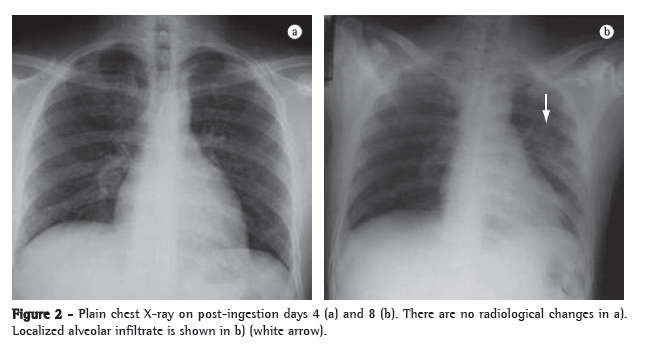

Chest X-ray findings at admission were normal (Figure 2a). Although the patient was not admitted until post-ingestion day 4, the sodium dithionite urine test result (for paraquat) was still positive at admission. He was submitted to hemodialysis and immunosuppressive therapy with cyclophosphamide, methylprednisolone, and dexamethasone, according to the protocol recommended by Lin et al.(3) In addition, he received N-acetylcysteine.

On the second day of hospital admission (post-ingestion day 6), the patient presented hemoptysis. A chest X-ray taken on post-ingestion day 8 showed localized alveolar infiltrate (Figure 2b). Pulmonary opacities, pneumomediastinum, pneumothorax, and subcutaneous emphysema were detected on a chest CT scan (Figure 3). On the seventh day of hospital admission, pulmonary gas exchange parameters worsened (Figure 1), and the patient was submitted to a second course of the same immunosuppressive therapy. Subsequently, despite of an episode of febrile neutropenia, he gradually recovered and was discharged four weeks later in good condition, with no need for home oxygen therapy. Four months later, the patient was working again and had no complaints, except for dyspnea after intense physical exertion. On chest auscultation, crackles were still heard in the lower lung fields, and there was wheezing throughout, together with pleural rub in the right hemithorax. The chest CT scan at four months after discharge is also shown in Figure 3.